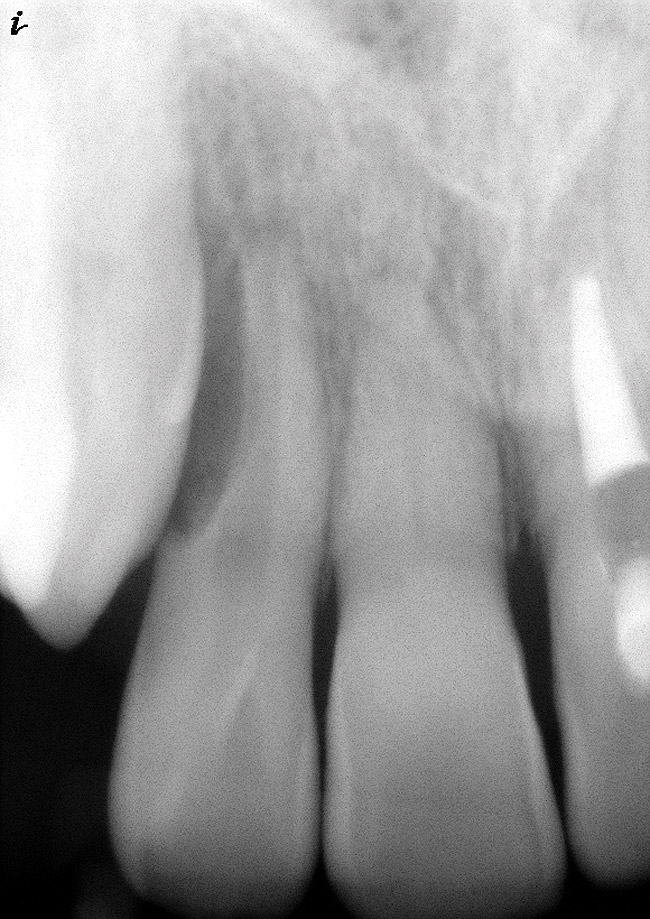

Figure 6  Root resorption secondary to orthodontic tooth movement.

Figure 6

Figure 7  Clinical case of internal root resorption that was treated by orthograde root canal therapy.

Figure 7

Figure 8  Clinical case of internal root resorption that was treated by orthograde root canal therapy.

Figure 8